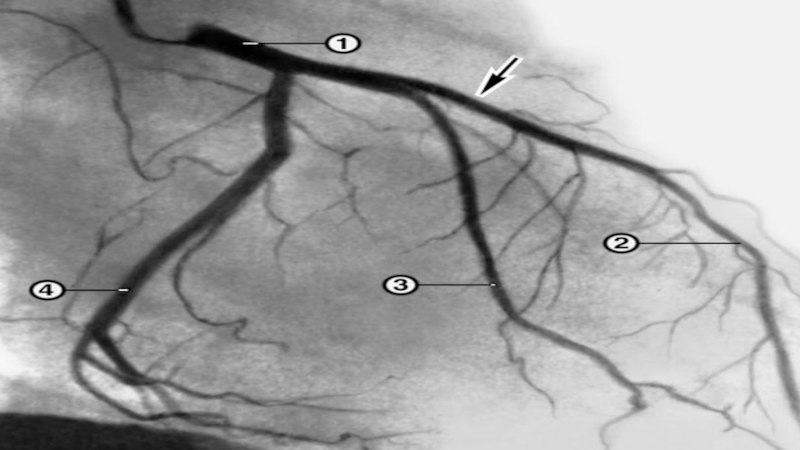

Слайд 27Ангиография

локализация стеноза (окклюзии)

сегментарный уровень стеноза

степень стеноза (% стеноза по диаметру,

% по площади, гемодинамическая значимость: до 50% - гемодинамически незначимые

50-70% - пограничные стенозы, 70% - и выше – критические стенозы,100% - окклюзия)

длина пораженного участка (короткий, длинный, диффузный)

конфигурация и анатомия поражения

количество пораженных артерий

морфология стеноза

коллатеральное кровообращение

степень перфузии в сосуде

Слайд 28Ангиография

Хирург при проведении ангиографии должен прекрасно ориентироваться в рентген анатомии

сосудов исследуемого органа, т.к. для получения наиболее достоверной информации о

поражении сосудов необходимо производить ангиографию в различных проекциях.

Например:

1. Правая передняя косая с каудальной ангуляцией

2. Правая передняя косая проекция с краниальной ангуляцией

3. Левая передняя косая с краниальной ангуляцией

и т.д.